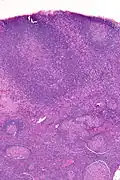

| Micrograph of a lymph node biopsy showing progressive transformation of germinal centres. H&E stain. | |

Microscopic appearance

PTGCs is characterized by:[1]

- follicular hyperplasia (many follicles),

- focally large germinal centres, with poorly demarcated germinal centre (GC)/mantle zone interfaces (as GCs infiltrated by mantle zone lymphocytes), and

- an expanded mantle zone.